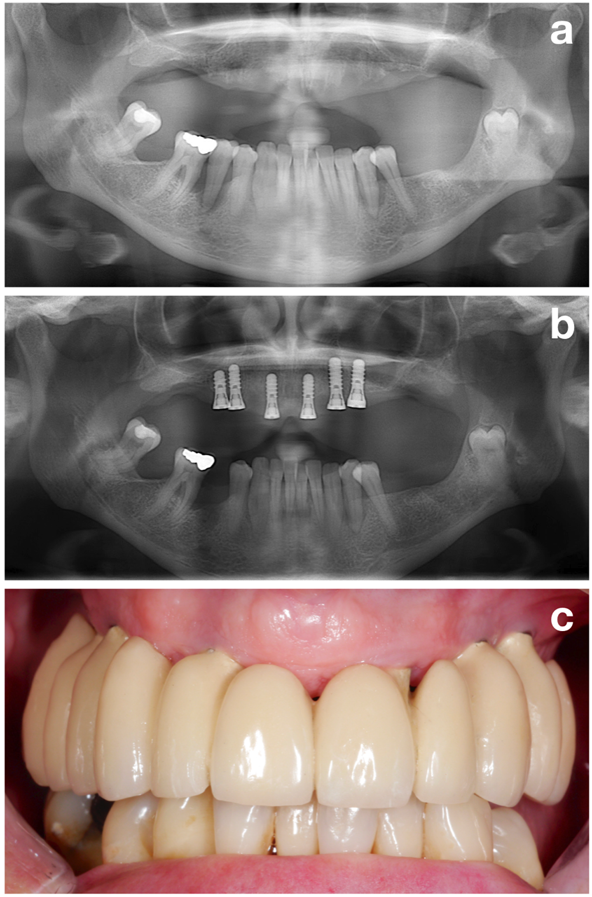

The first part (i.e., the pre-treatment phase) aims to perfectly prepare the patient for the actual implant installation by evaluating all potential risk factors but focusing on one of the most important ones: establishment of a stable periodontal situation (Figure 2).

In conclusion, establishing a stable periodontal situation is next to other aims, such as smoking cessation or perfect oral hygiene (Figure 3), one of the most important goals in the pre-treatment phase, which should be achieved prior to implant installation!